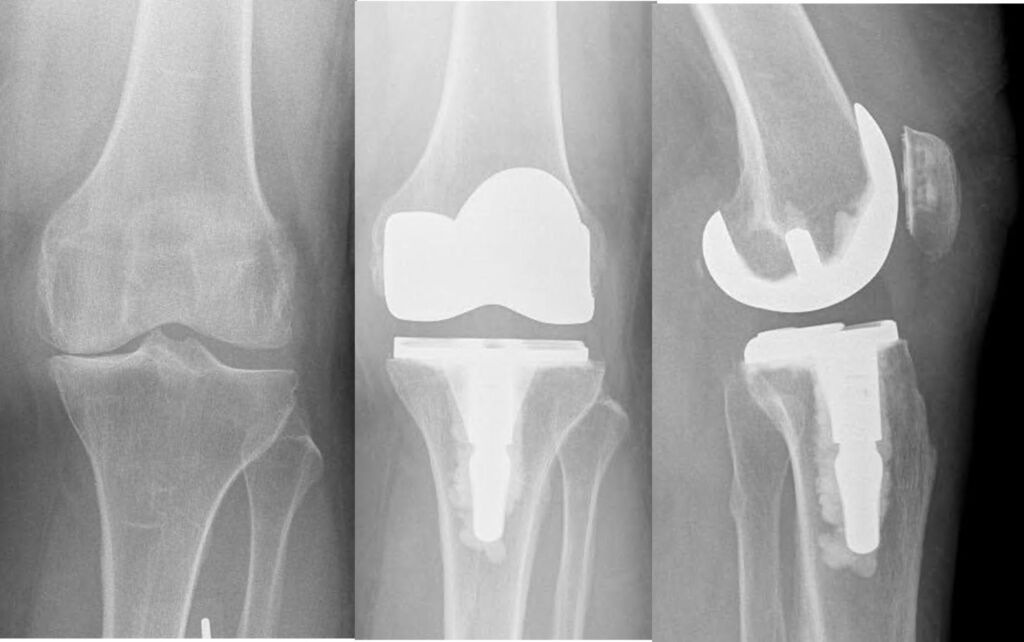

JOINT REPLACEMENT / ARTHOPLASTY

Advanced knee arthritis – left image,

Total knee replacement – right image